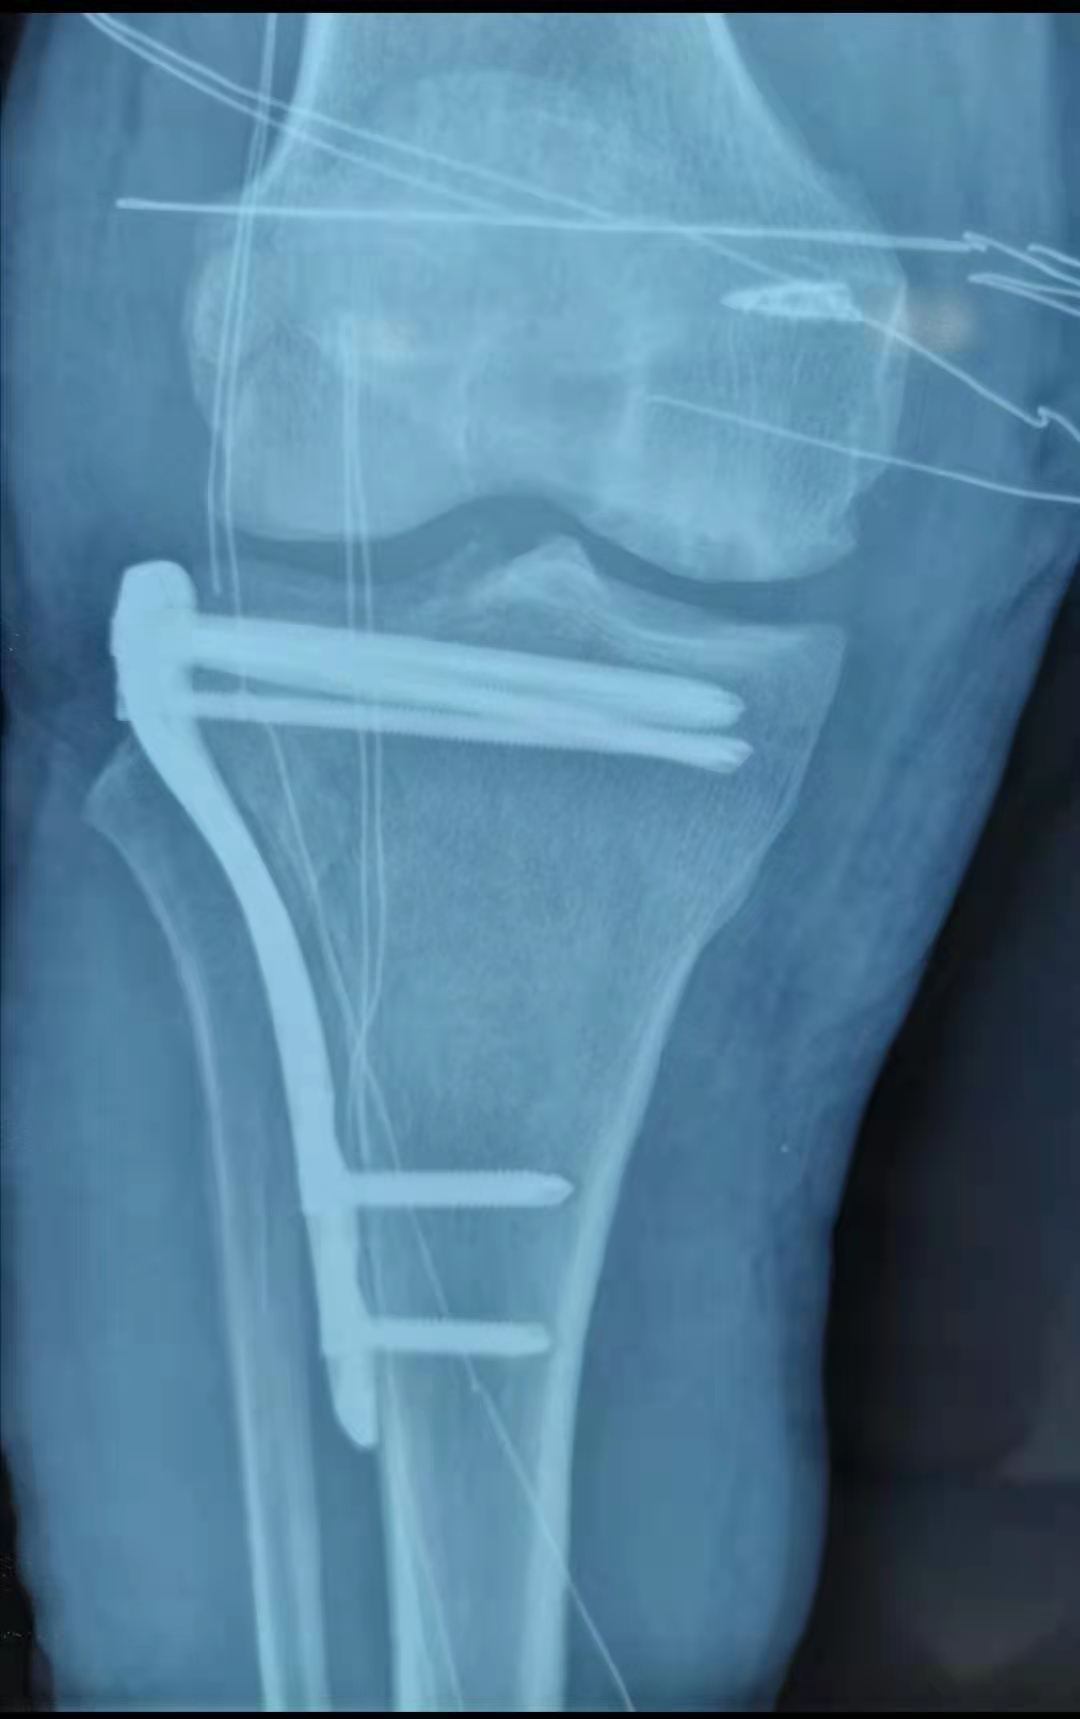

Schatzker Ⅲ型胫骨平台骨折是指单纯的外侧胫骨平台中央凹陷型骨折,属于关节内骨折,其骨折复位要求达到解剖复位,而膝关节内 解剖结构较为复杂,手术难度较大。

近日,涡阳县人民医院骨一科袁彬副主任和程庆主治医师开展利用关节镜辅助复位、锁定钢板内固定治疗Schatzker Ⅲ型胫骨平台骨折,实现精准复位,减少了对关节的激惹,获得良好效果。

该手术采取小切口、胫骨平台外侧开窗后,在关节镜辅助下直视塌陷处,利用顶棒使塌陷关节面复位,从而达到真正的解剖复位,同时进行打压植骨,再利用锁定钢板固定,使塌陷关节面获得良好支撑,患者术后第一天支具保护下锻炼,获得良好效果。